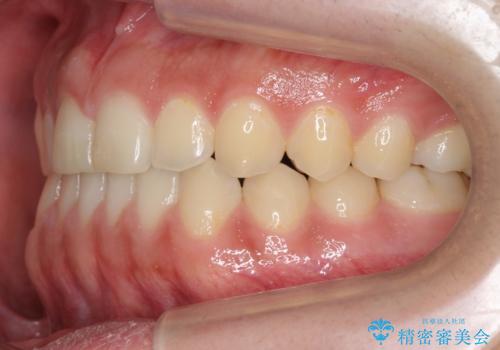

前歯のすきま 受け口 インビザラインで

- 前歯のすき間を気にして来院。

受け口もあり、前歯が端同士であたる、切端咬合となっていました。

下の歯のすき間を閉じて上の歯の内側に入るように位置付けました。

すき間もきれいに閉じ、満足していただきました。

上の前歯は下の歯と直接へりが当たっていた状態(切端咬合)だったため、形がいびつだったのは、わずかにやすりがけをして整えました。